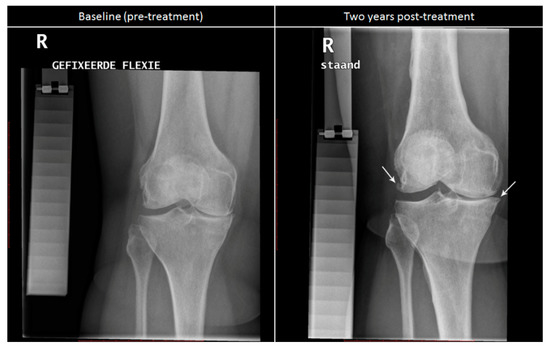

3.2. Changes after Knee Joint Distraction